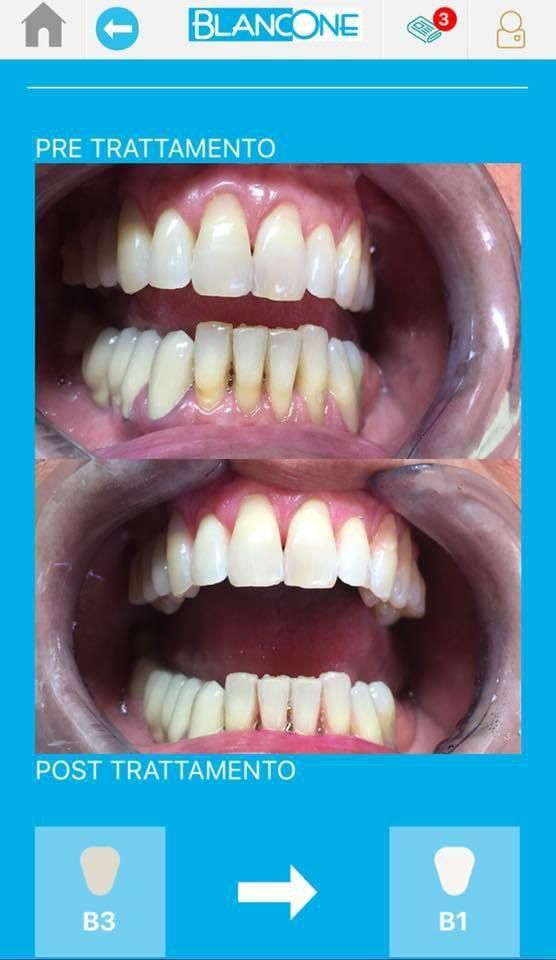

Foto e video